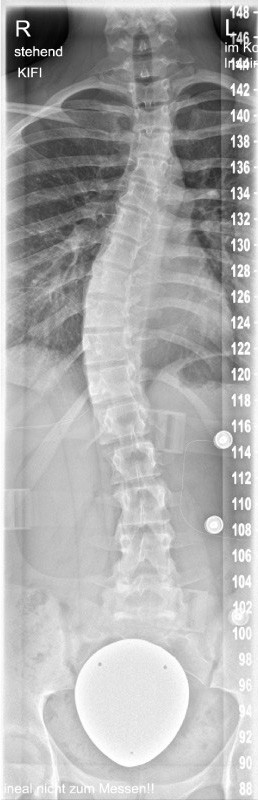

an der Wirbelsäule

• Wirbelsäulenverkrümmung

• Skoliose (Bild)

Skoliose